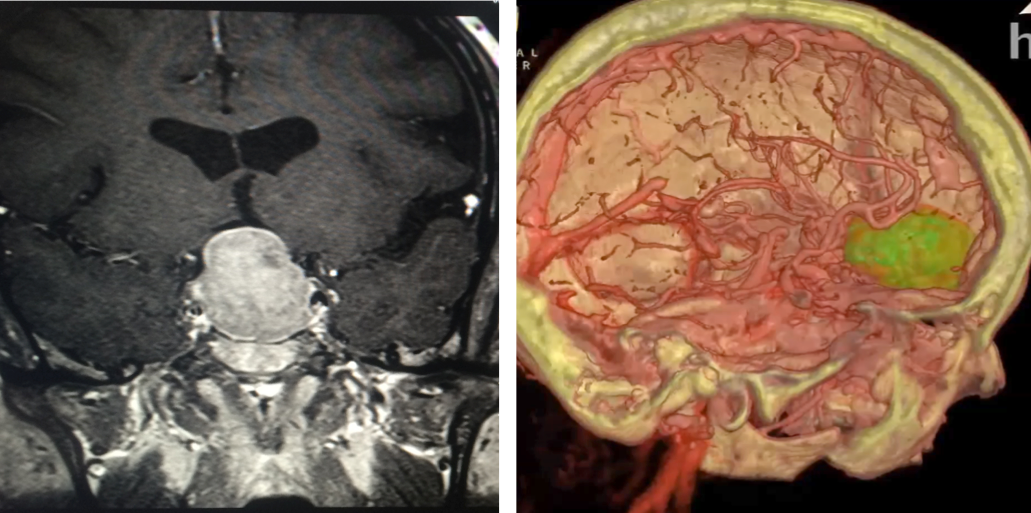

Slice v 3D: Patients and surgeons at Hoag Memorial Hospital are looking at virtual reality reconstructions (right) over conventional 2D images. Images courtesy of Hoag Memorial Hospital

Patients better understand their treatment, he said. “Patients who used to rely on black-and-white images (MRI and CT slices) now can do a 3-D fly through of their own brains,” he said.

Clinical technicians at Surgical Theater, which sold the VR technology to Hoag Memorial Hospital, assemble 360-degree VR models from standard cross-sectional MRI and CT brain slices acquired preoperatively. Louis noted that the VR models require some effort to bring into the workflow but that understanding these models is “really intuitive.”

The high-resolution reconstructions immerse patients and physicians in the patient anatomy. Key metrics demonstrate how VR benefits both.

The graphic power of the technology is obvious, exemplified by virtual “fly-throughs” of patient brains at Hoag Memorial Hospital. These fly-throughs show colorized representations of arteries and nerves along the chosen route to the tumor. These are the same structures that neurosurgeons would see endoscopically during minimally invasive brain surgery, according to Louis, who uses “keyhole surgery” to minimize damage to healthy brain, vascular and soft tissue structures. (The approach is so-named because it is akin to looking through an old-style keyhole of a door, through which “you could see the entirety of what was on the other side, as opposed to opening the door,” Louis said.)